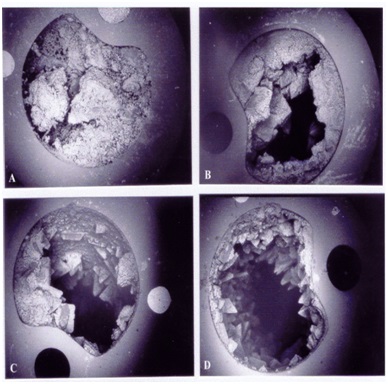

细菌生长在晶体上与晶体之间

形成堵塞的导管的横结截面